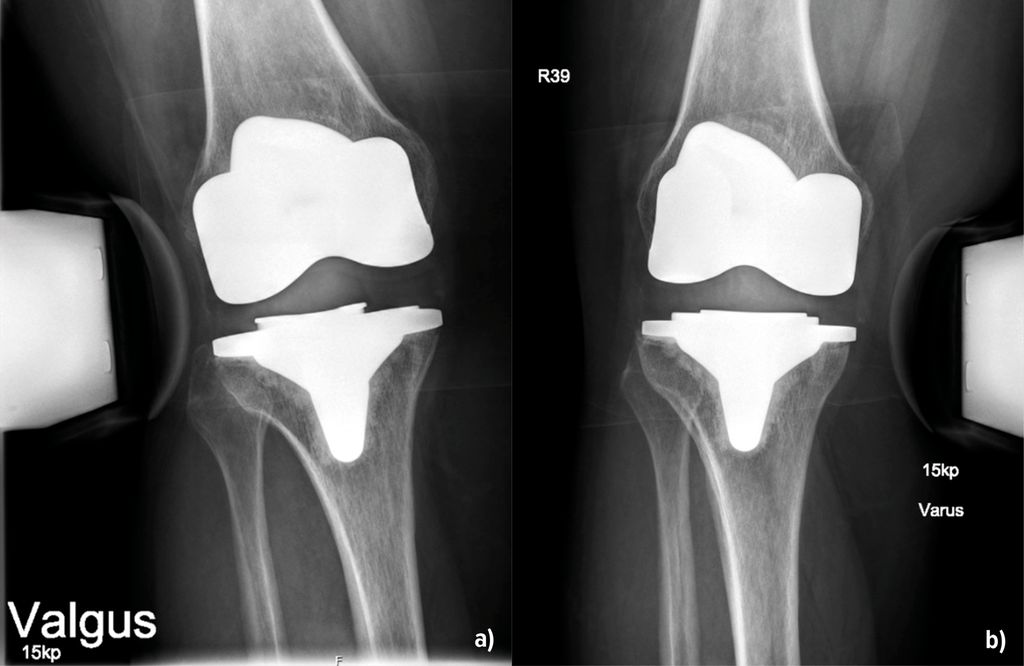

Abb. 1:Instabilität infolge eines Verschleisses. Im ap. Röntgenbild (a) sind die vermehrte laterale Aufklappbarkeit und die mediale Verschmälerung des Gelenkspaltes gut sichtbar. Das Inlay weist deutliche Verschleissspuren auf (b). Nach dem Wechsel auf ein neues Inlay in primärer Höhe ist im Röntgenbild der Gelenkspalt wieder gleichmässig dargestellt (c)

Die Balancierung von Extensions- und Flexionsspalt ist von essenzieller Bedeutung für die Vermeidung von Instabilitäten. So führt die Resektion des hinteren Kreuzbandes zu einer Flexions-Extensions-Diskrepanz. Dabei vergrössert sich der Flexionsspalt stärker als der Extensionsspalt, wobei die Zunahme des lateralen Flexionsspalts ausgeprägter ist als medial. Daraus resultiert eine mediolaterale Instabilität in Flexion (Kayani et al. 2019), was primär durch die Verwendung von PS-Inlays vermieden werden kann (Zhang et al. 2024). Parisch et al. (2025) konnten in einer konsekutiven Gruppe von 172 Knietotalendoprothesen mit kompletter oder isolierter Flexionsinstabilität nachweisen, dass für die globale Instabilität (Instabilität in Flexion und in Extension) ein Inlaywechsel die geeignetste Therapie ist, für eine isolierte Flexionsinstabilität jedoch der komplette Wechsel. Die «einfache» Instabilität lässt sich somit unter Adressierung von globaler bzw. isolierter Flexionsinstabilität sehr gut behandeln: entweder mit einem Inlaywechsel bei globaler Instabilität unter Verwendung einer höheren Inlay-Komponente (Abb.1) oder durch eine stärkere Kopplung des Knieprothese bei isolierter Flexionsinstabilität.